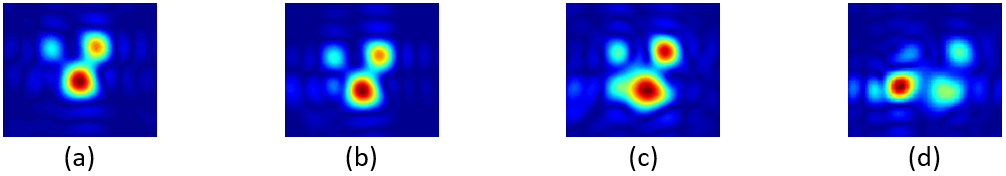

In this collaboration, EPR imaging technology is demonstrated to be a novel physiological imaging modality useful in obtaining maps of tissue oxygenation quantitatively and non-invasively with high spatial and temporal resolution. In vivo EPR imaging has been successfully implemented in small animal experiments, specifically in mouse models of human cancer to obtain information (e.g., dynamics of tumor physiology, hypoxia) critical for treatment selection (e.g., chemotherapy, anti-angiogenic drug therapy, and radiotherapy) and response monitoring. The capabilities of EPR imaging have been found to be very useful in screening anti-cancer agents, as well as understanding their mechanisms. The NIH development team, NCI Radiation Biology Branch and CIT SPIS, has designed and implemented several EPR imaging systems capable of in vivo imaging, which is often combined via co-registration with anatomic images from MRI.

The imaging systems and methodologies (e.g., microscopic histopathology for microvessel analysis) are utilized by many NIH scientists. Prior techniques, which provided such information, are either invasive or not quantitative, and there is no equivalent commercially available EPR imaging system. In contrast to MRI, EPR imaging requires lower radio-frequency (RF) power levels, faster data acquisition rates, and very sensitive detectors. SPIS engineering and prototyping expertise has been critical to addressing these hardware and software design requirements.

Rapidscan EPR has some of the best attributes of the other two modalities. It offers the sensitivity of CW EPR and the faster data acquisition rates of pulsed EPR. Since the RF signal is constant, data acquisition is not hampered by dead time and coil resonant ringing. The gradient and B0 fields oscillate sinusoidally making them simple to generate. Overall, the hardware requirements for Rapidscan EPR are easier to achieve.